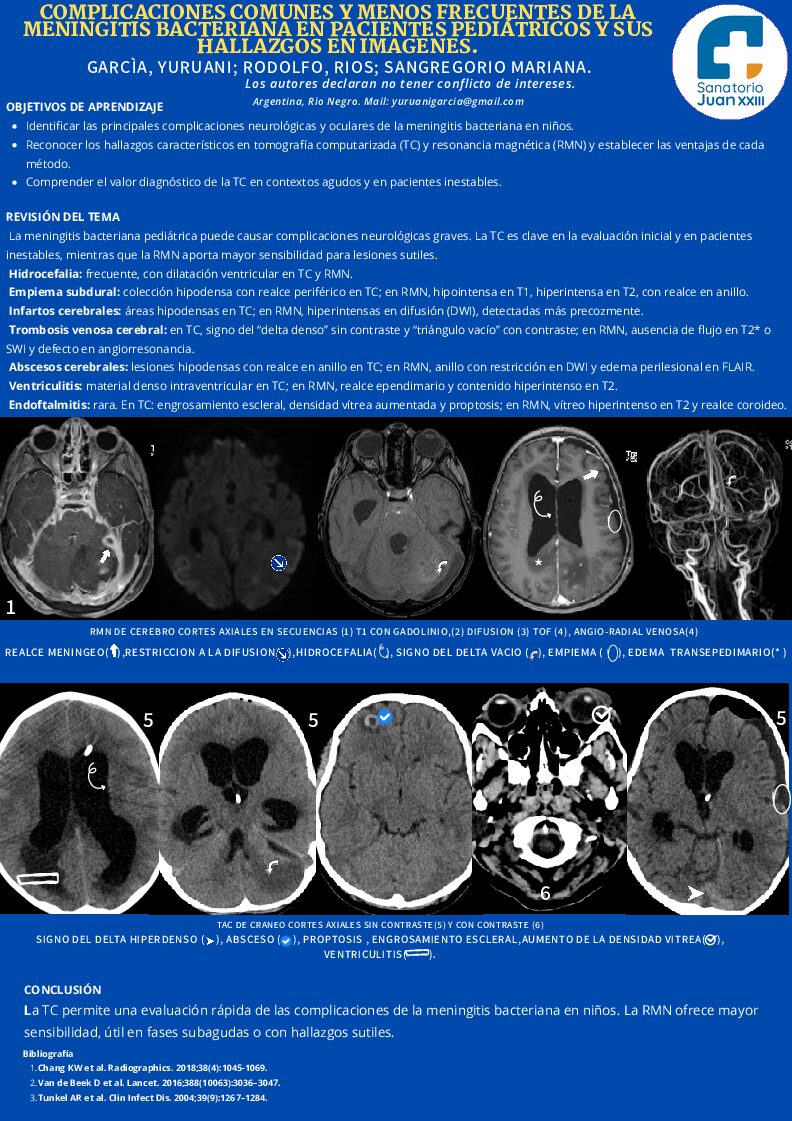

COMPLICACIONES COMUNES Y MENOS FRECUENTES DE LA MENINGITIS BACTERIANA EN PACIENTES PEDIÁTRICOS Y SUS HALLAZGOS EN IMAGENES